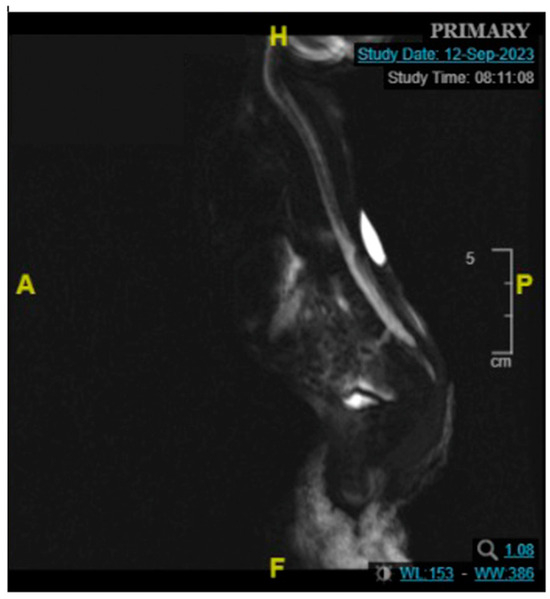

2.1. Patient 1

2.2. Patient 2

2.3. Patient 3

2.4. Patient 4